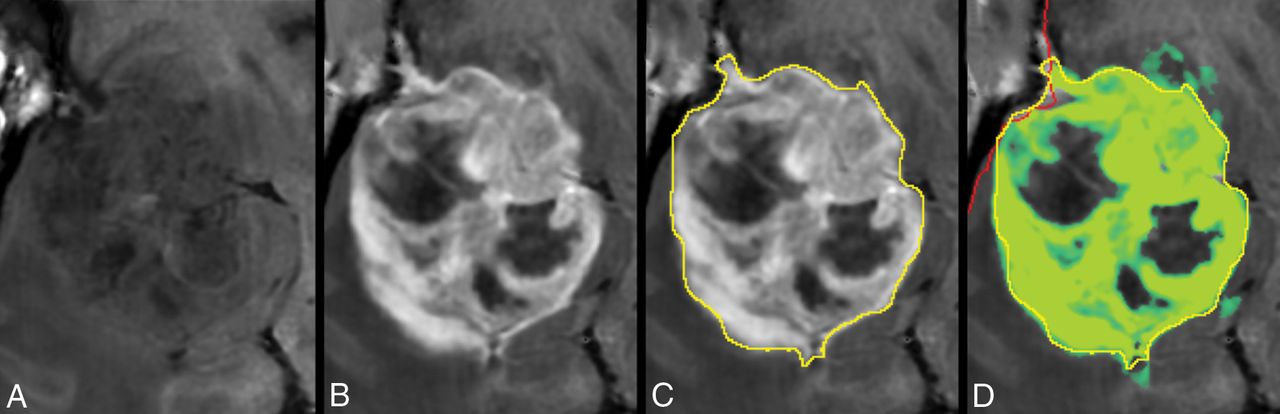

In Fig 4, the tumor in Fig 2 is zoomed-in. The native and post-GBCA T1-weighted images are shown as well as the ROI drawn by the radiologist. In Fig 4D, the synthetic R1 enhancement map is shown as a green overlay where full color corresponds to a dR1 of 1 second−1. At various places, low-intensity enhancement in the range 0.2–0.5 seconds−1 is observable outside the high-intensity enhancing tumor and drawn ROI. On average for all patients, 35.8% of the pixels touched by the drawn ROI lines had values above 0.2 seconds−1 for the synthetic R1 enhancement map and even 50.3% for the subtraction R1 enhancement map. When the ROI line was expanded with an additional margin of 1 or 2 mm, this percentage reduced to 8.0/17.4% and 2.3/8.6%, respectively (Table 2).

Zoomed part around the tumor displayed in Fig 2. Synthetic T1-weighted imaging using native data (A), synthetic T1-weighted imaging using post-GBCA data (B), the ROI line as drawn by a neuroradiologist to encapsulate the border of the enhancing tumor (C). D, Synthetic R1 enhancement map shown as a green overlay on the synthetic T1-weighted image in which full color corresponds to dR1 = 1.0 seconds−1. The minimum enhancement was set at dR1 = 0.2 seconds−1. Some low-intensity enhancement is visible outside the yellow ROI. The red line indicates the edge of the intracranial volume.

To illustrate the perception of a radiologist, we drew ROIs to encapsulate the enhancing part of the tumor. For our 14 subjects, 36% of the pixels touched by the ROI line had dR1 values above the chosen threshold of 0.2 seconds−1, with a mean enhancement of 0.48 seconds−1. For the subtraction R1-enhancement map, it was 50%, with similar mean enhancement. This indicates that the perception of the trained eye to determine R1 enhancement is on the order of 0.2–0.5 seconds−1, corresponding to 10%–25% of the maximum enhancement. Further studies, with more readers are required to verify this value, but it shows that low-intensity enhancement in a T1-weighted image is easily rated as nonenhancing, which can affect the diagnosis.20,21 It is well-known that high-grade gliomas infiltrate into the peritumoral edema,3,16 which can be detected with higher sensitivity using diffusion22 or a multiparametric approach.23 In our study, the application of an additional peritumoral margin of 1 or 2 mm rapidly reduced the number of pixels above the threshold as well as the mean dR1 on the ROI line. For those pixels that did have values above 0.2 seconds−1, however, the mean dR1 was 0.3–0.4 seconds−1, indicating that the enhancement was highly localized. Examples are shown in Figs 4 and 5. Low-intensity enhancement at the tumor edges is not distributed equally on all sides; it occurs mainly in a limited number of focal areas. In a previous study, we showed a gradient of R1 relaxation at the edge of enhancing tumors.16 The current study indicates that the detected gradient was likely to be a composition of no-gradient areas and high-gradient areas.